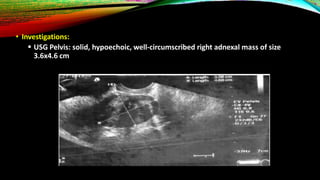

• Investigations:

ď‚§ USG Pelvis: solid, hypoechoic, well-circumscribed right adnexal mass of size

3.6x4.6 cm

• Investigations:  USGPelvis: solid, hypoechoic, well-circumscribed right adnexal mass of size 3.6x4.6 cm